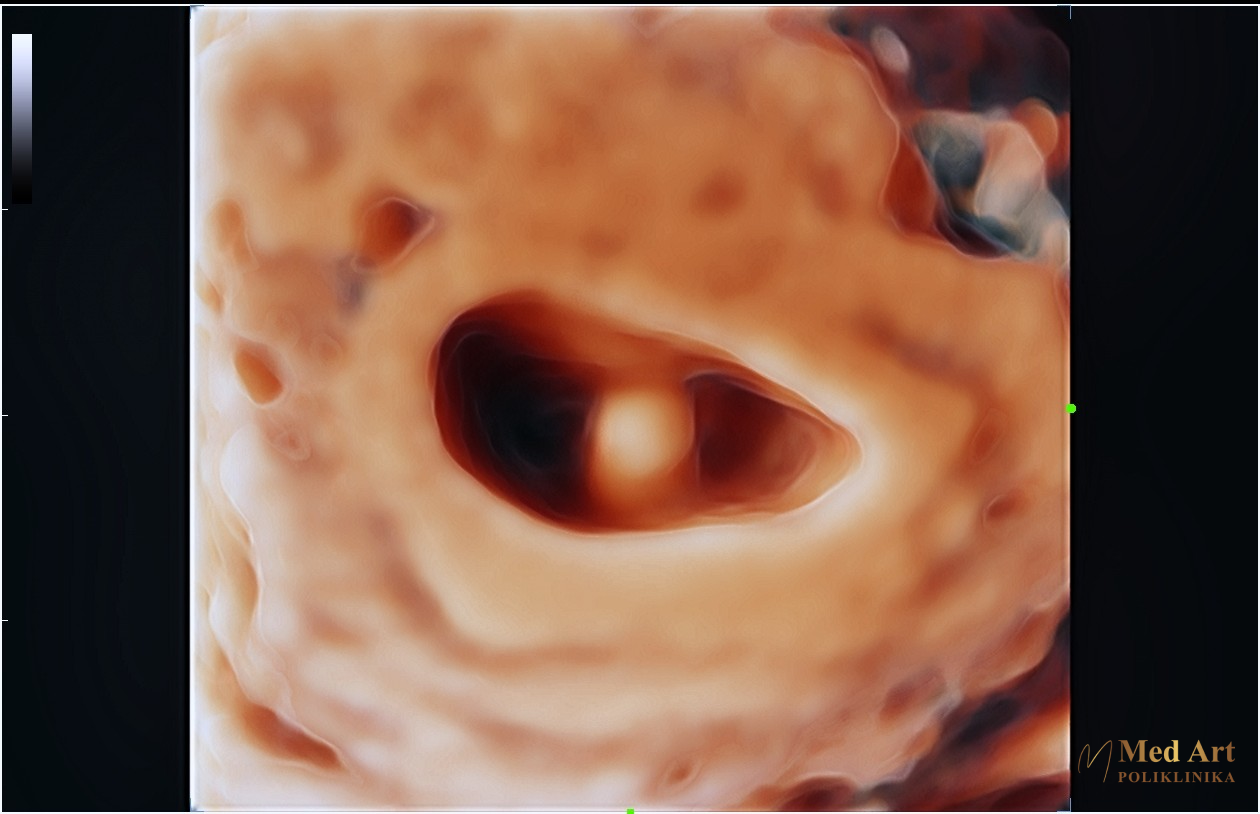

U galeriji koja slijedi, možete vidjeti ultrazvučne slike beba u 6., 7., 8., 12., 14., 20., 21., 24., 27. i 34. tjednu trudnoće, koje prikazuju njihov razvoj od rane trudnoće pa sve do priprema za dolazak na svijet.